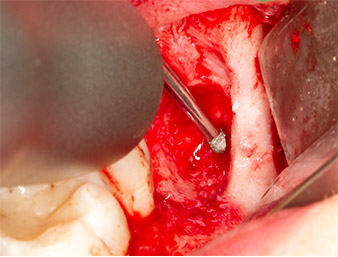

Using an instrument for periodontal debridement (Piezomed P1), the periodontal ligament space of the radix relicta was then widened minimally (Fig. 8).

The same activated instrument was inserted into the root canal and loosened the fragment as a result of its micro-oscillating vibrations (Fig. 9, 10).

Piezomed P1

Fig. 9: The Piezomed P1 instrument is recommended by the manufacturer primarily for periodontal debridement but is also suitable for surgical purposes. Here it is placed in the root canal after minimal widening of the periodontal ligament space.